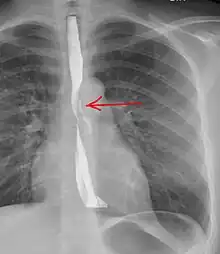

Perforation of the esophagus as seen on esophagogram

The diagnosis of Boerhaave's syndrome is suggested on the plain chest radiography and confirmed by chest CT scan. The initial plain chest radiograph is almost always abnormal in patients with Boerhaave's syndrome and usually reveals mediastinal or free peritoneal air as the initial radiologic manifestation. With cervical esophageal perforations, plain films of the neck show air in the soft tissues of the prevertebral space.

Hours to days later, pleural effusion(s) with or without pneumothorax, widened mediastinum, and subcutaneous emphysema are typically seen. CT scan may show esophageal wall edema and thickening, extraesophageal air, periesophageal fluid with or without gas bubbles, mediastinal widening, and air and fluid in the pleural spaces, retroperitoneum or lesser sac.